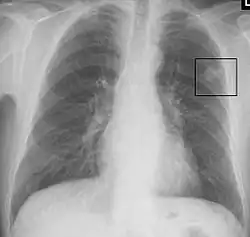

Radiografía simple de tórax

En las radiografías simples de tórax se puede observar alguna anormalidad en casi el 98 % de los pacientes con un carcinoma broncogénico, y el 85 % son imágenes sugestivas para sospechar el diagnóstico por las alteraciones pulmonares distales (atelectasia), la existencia de adenopatías (ensanchamiento mediastínico) o detección de invasión de la pared torácica. La radiografía de tórax detecta elementos sospechosos en la mayoría de los pacientes con tumores pulmonares.[133] No se recomiendan las tomas radiológicas en serie para la detección temprana del cáncer de pulmón.[121]